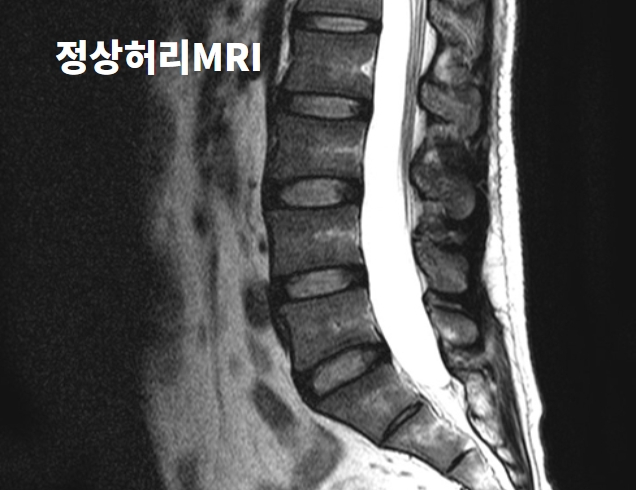

허리디스크의 정확한 명칭은 '요추 추간판탈출증'입니다.

허리는 몸을 지탱하는 대들보인데 5개의 척추 뼈 사이의 물렁뼈를 디스크(추간판)라고 합니다.

이 디스크가 튀어나와 다리로 가는 신경을 자극하면 통증이 생깁니다.